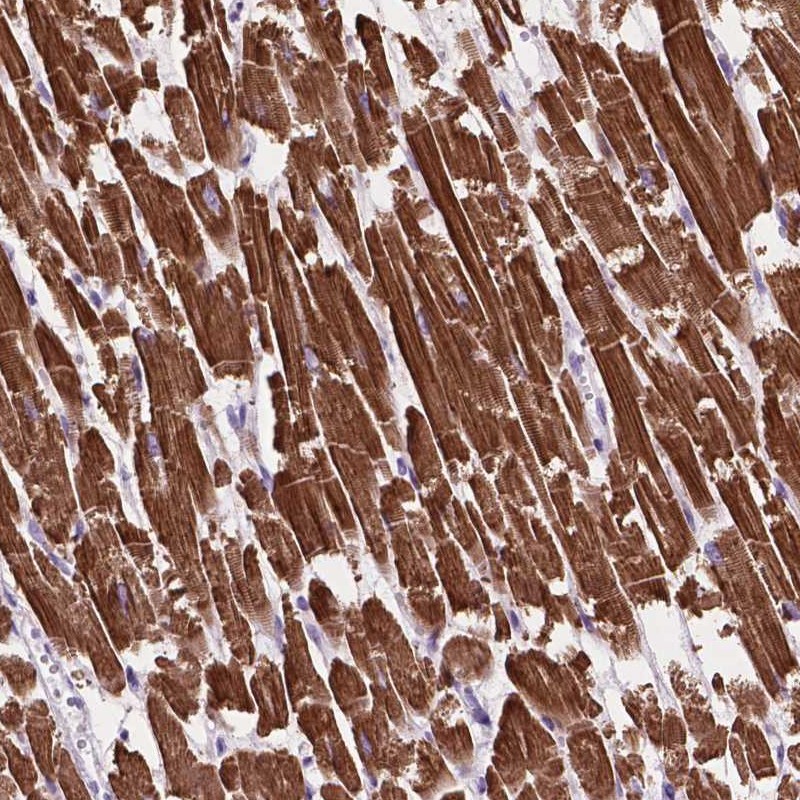

Immunohistochemical staining of human heart muscle shows strong cytoplasmic positivity in myocytes.